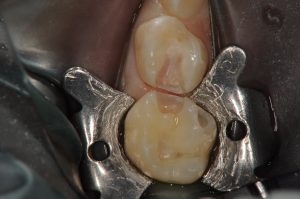

今回は、大学病院当時の症例として虫歯がある状況と虫歯を完全に除去した時の写真をあげようと思います。

削ってない方は、見ると、歯に黒い部分がありますが、そんなに大きくないようにも見えると思います。

しかし、削った後の写真を見て見ると、上の歯は、歯の1/2以上を削っている状態であり、神経までギリギリの状態となっております。

もちろん、この子も実際に、痛いなどという症状は一回も感じていないようです。

このケースももちろん麻酔を行い処置をしております。